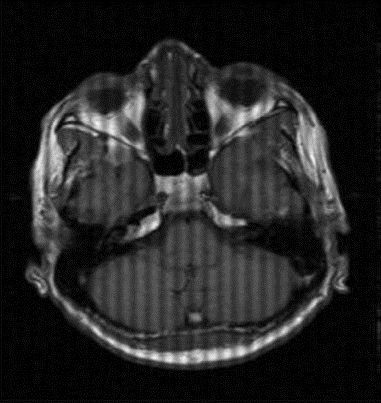

k-space data error (herringbone)

A single erroneous data point (spike) in k-space creates a line pattern through the image

if data point is on the x-axis the lines will be verticle, if the data point error is on the y-axis the lines will be horizontal. If the lines are diagonal, the data error is not on an axis.

how to fix: Repeat the scan without parameter changes (usually due to random error). But, if it occurs frequently as faulty coil may be the problem

k-space data error (herringbone artifact)

Due to a data flitch/ reconstruction error

To fix this just reconstruct again and hopefully the error in k-space will resolve